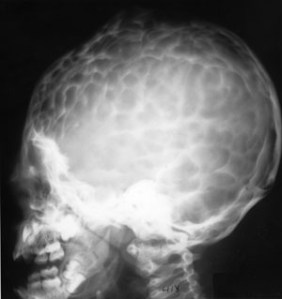

SIGNO DEL BRONCE BATIDO

El nombre de cráneo en bronce batido (o también cobre batido) hace referencia al aspecto de los huesos craneales con marcado aumento del patrón de circunvoluciones. La causa está en el aumento de la presión intracraneal que puede ser debido al cierre precoz de las suturas (craneosinostosis), hidrocefalia obstructiva, masas intracraneales o hipofosfatasia.

Este otro caso, reciente, me lo ha enviado mi compañera la Dra. Irene Bocanegra, del H. Materno-Infantil de Málaga. Muchas gracias por su aportación.